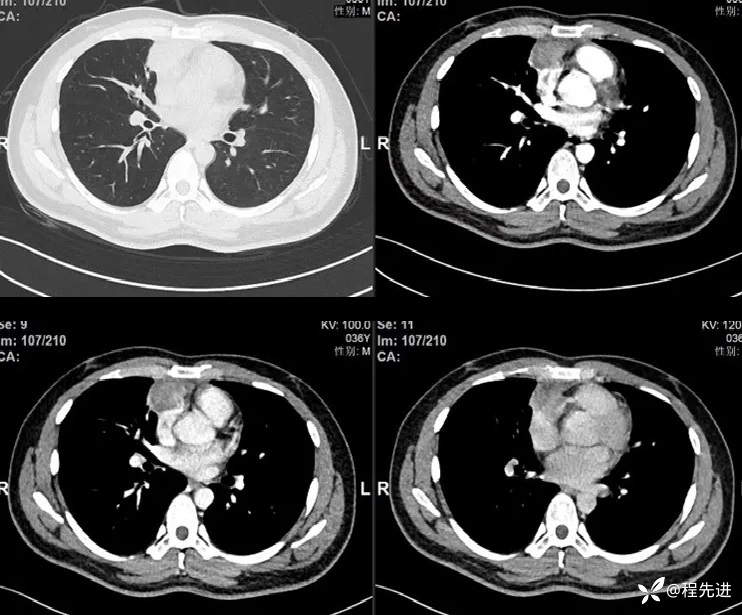

患者性别:男

患者年龄:36岁

主诉:胸痛1个月

现病史:患者1月前偶有胸痛,行胸部CT检查提示前纵隔占位性病变。病来饮食睡眠可,二便正常,体重无明显变化。